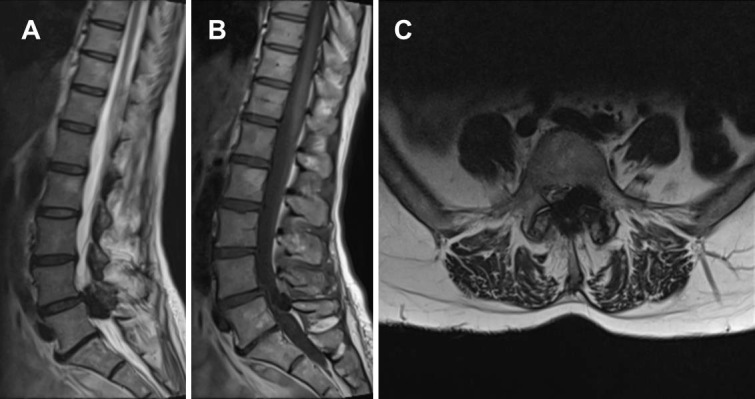

Severe Spinal Stenosis Secondary to a CREST Syndrome Related Calcific Deposit: A Case Report.